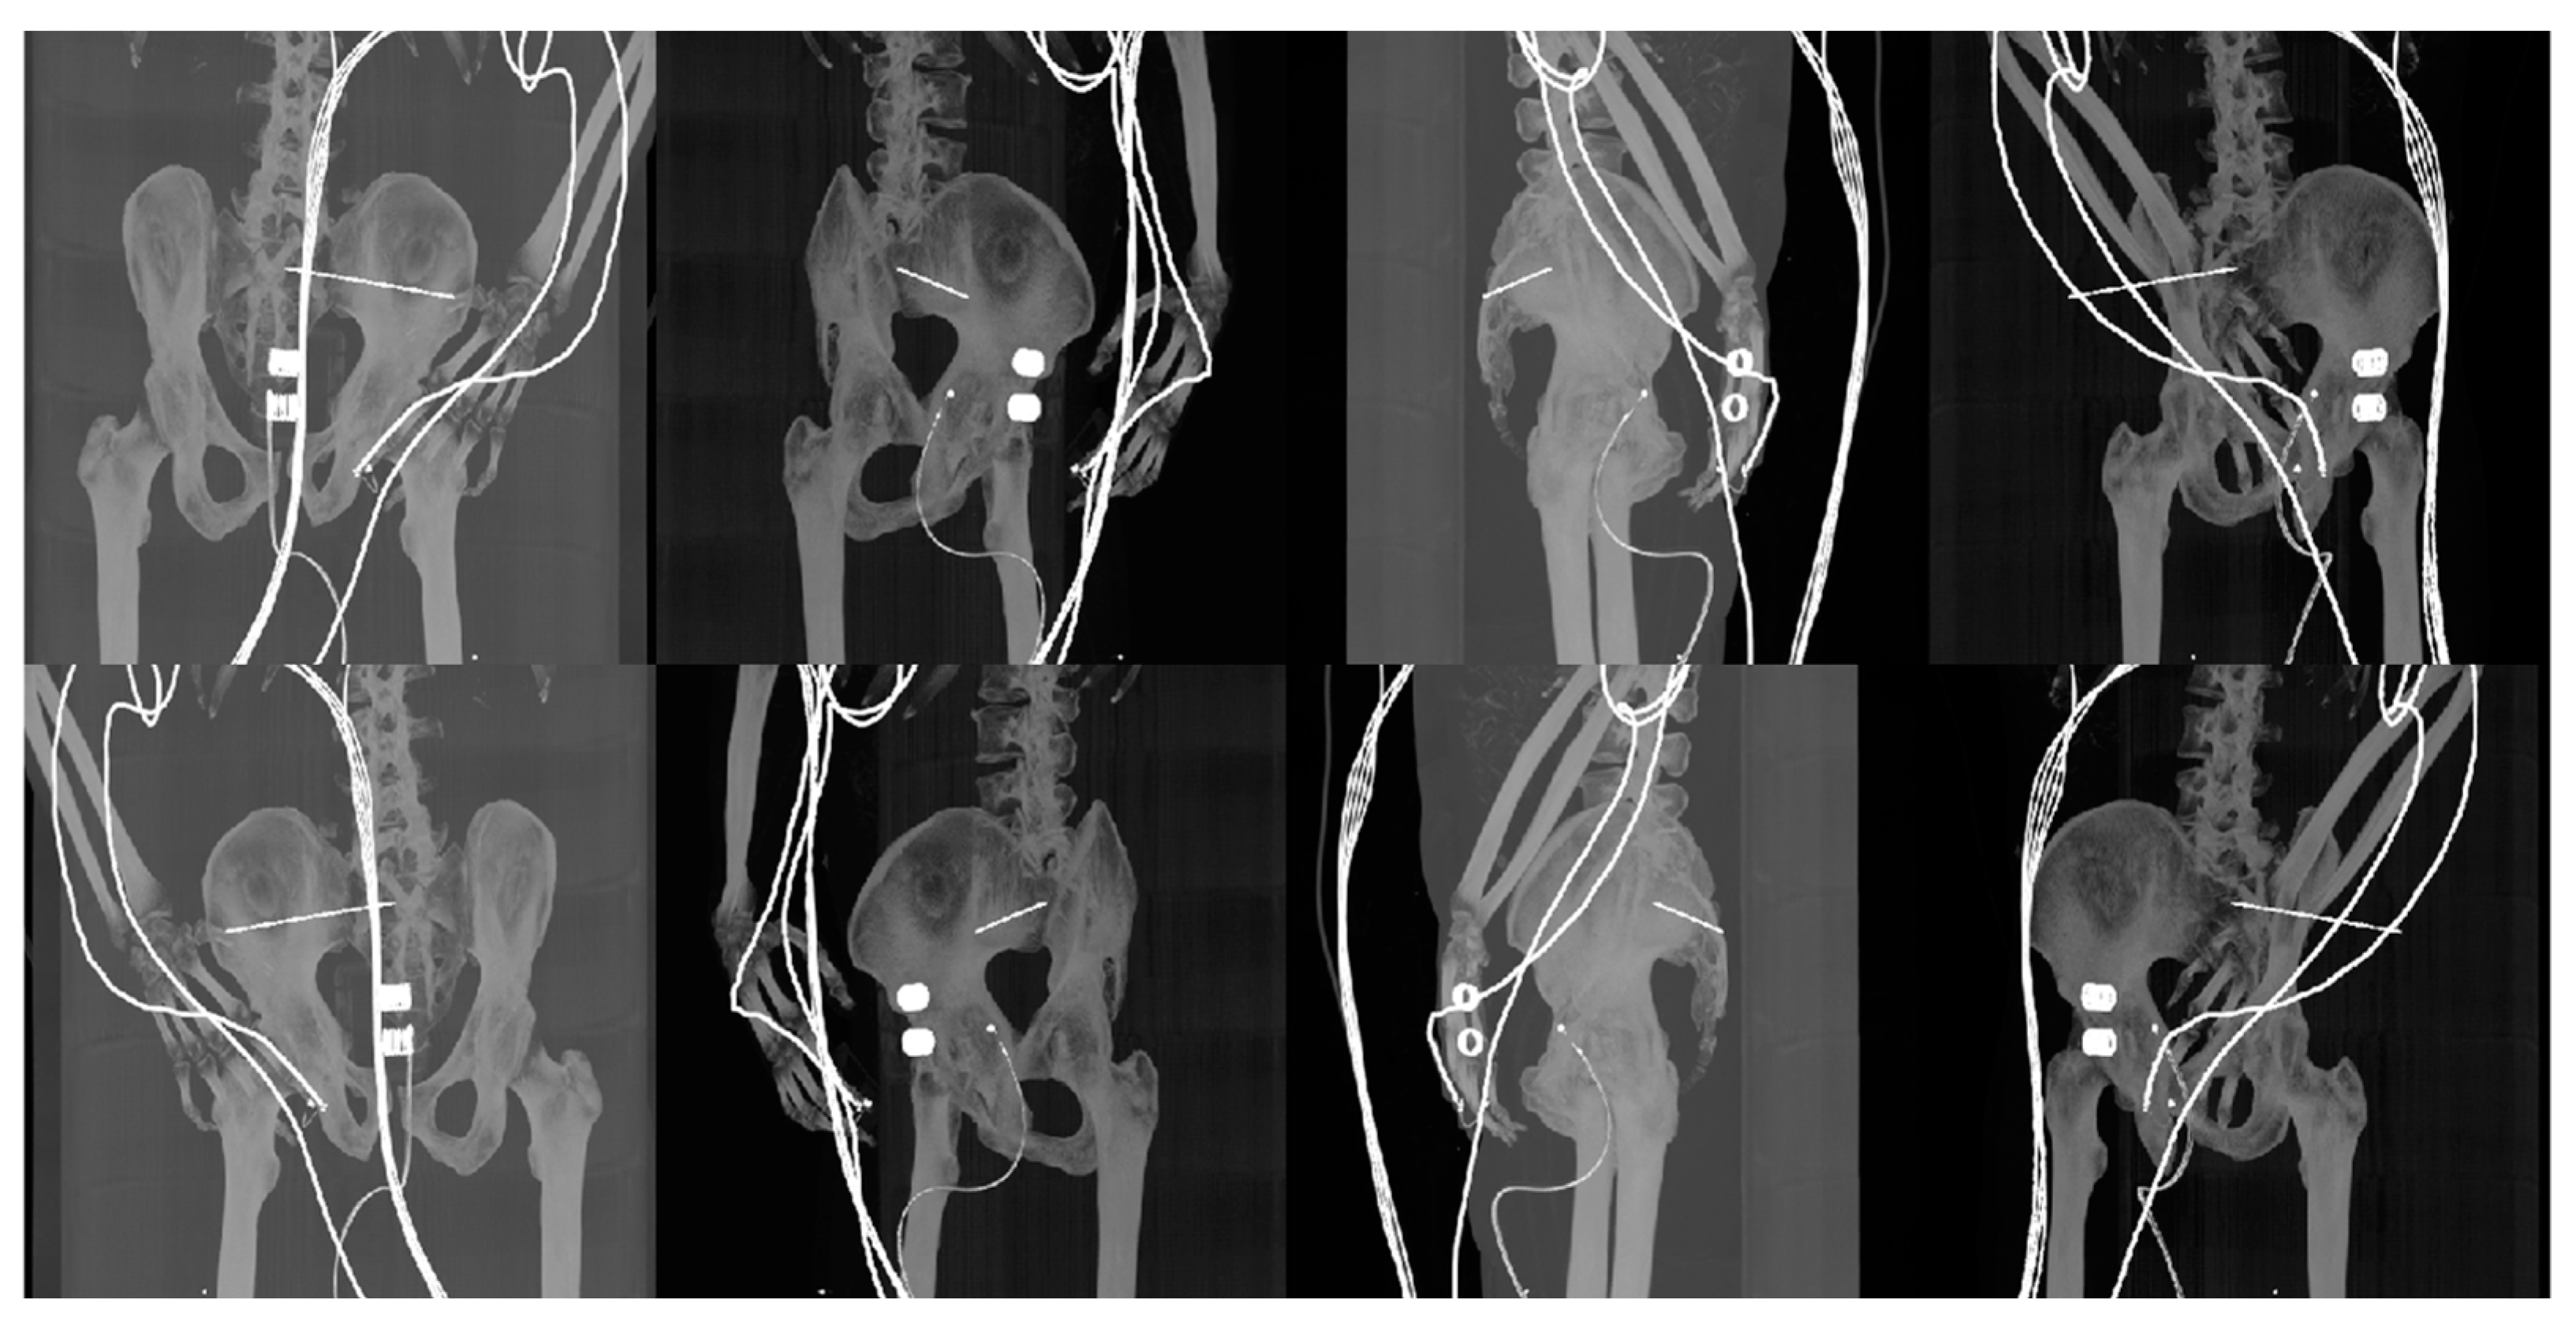

- Reconstructed DDR projections with virtual iliosacral screw

- Generation of digitally reconstructed radiograph (DRR) projections